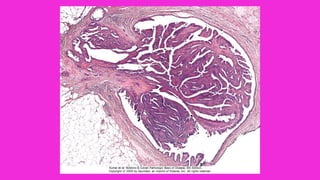

ECTASIA DUCTAL MAMARIA

• Morfología La lesión se caracteriza principalmente por

dilatación de los conductos, espesamiento de las

secreciones mamarias y una marcada reacción

inflamatoria granulomatosa crónica periductal e

intersticial.

• Los conductos dilatados están llenos de detritos

granulosos que contienen infiltrados densos de

linfocitos y macrófagos y un número variable de células

plasmáticas.

• En ocasiones se forma inflamación granulomatosa

alrededor de lo depósitos de colesterol.

• La fibrosis puede acabar produciendo retracción de la

piel y el pezón.